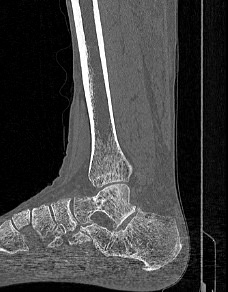

Костные ткани хорошо поглощают лучи рентгена, поэтому ярко визуализируются на снимках. В результате цифровой обработки полученных данных получаются точные трехмерные объемные модели исследуемой области. При этом изображение кости можно приблизить, повернуть в разные стороны, что значительно повышает точность диагностики заболеваний костного скелета.

В наших центрах проводится КТ различных отделов костного скелета. В протокол обследования 1 сегмента костного скелета входит прицельное исследование одной анатомической области. Например, КТ плечевой кости, КТ предплечья, КТ кисти, КТ стопы и других частей скелета.

Мультиспиральная КТ костей наиболее часто применяется в ортопедии, травматологии, хирургии, онкологии и ревматологии. Данное исследование позволяет диагностировать:

- Травматические повреждения костей скелета (различные переломы, ушибы надкостницы, вывихи, разрывы связок);